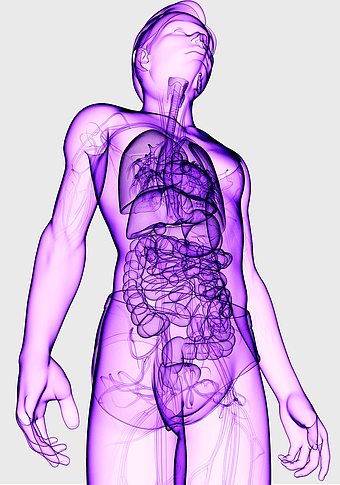

Human internal organs illustration, heart and lung anatomy, kidney and liver diagram, brain and stomach structure, medical organ chart, human body systems visual, educational anatomy graphics, PNG

- human internal organs illustration

- heart and lung anatomy

- kidney and liver diagram

- brain and stomach structure

- medical organ chart

- human body systems visual

- educational anatomy graphics

human digestive system, gastrointestinal tract anatomy, liver function, stomach and intestines, digestive health, internal organs diagram, human body systems -

female human organ model, human digestive system anatomy, gastrointestinal tract illustration, liver and stomach diagram, medical education visuals, anatomical study aids, human body internal structures -

human internal organs chart, gastroenterology anatomy diagram, electric blue human anatomy, liver and stomach illustration, digestive system visualization, medical organ study, human body internal structure -

human anatomy diagram, digestive system illustration, human internal organs, Homo sapiens muscular system, anatomical art for education, systemic physiology chart, medical biology graphics -

female anatomy diagram, human organ system chart, woman's body structure, female internal organs, human anatomy illustration, medical educational image, anatomical reference guide -

human anatomy illustration, human organ system diagram, human body internal organs, human digestive system, anatomical chart, medical illustration, physiological diagram -

blue human anatomy illustration, human circulatory system diagram, digital human skeleton image, electric blue medical figure, human nervous system visualization, human body organ map, human health care graphic -

human anatomy illustration, purple medical figure, human body healing art, quantum health visualization, anatomical organ depiction, therapeutic body diagram, violet human structure -